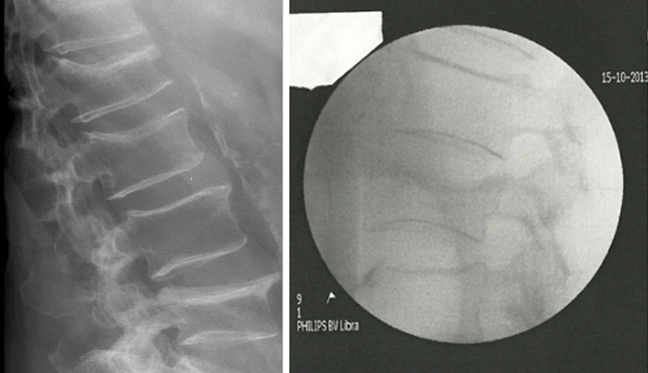

Τα κατάγματα της σπονδυλικής στήλης που συμβαίνουν μετά την ηλικία των 50 ετών, κυρίως σε γυναίκες, που οφείλονται σε οστεοπόρωση, μπορούν να συμβούν σε μια απλή πτώση, όταν σηκώσει κανείς απότομα ένα βάρος, ακόμη και αν τραβήξει ένα βαρύ συρτάρι.

Στα κατάγματα αυτά σπάνια επηρεάζεται κάποιο νεύρο. Το κύριο ενόχλημα είναι ο πόνος που μπορεί να είναι από υποφερτός μέχρι πολύ οξύς. Ο πόνος εμφανίζεται σ΄ όλες τις κινήσεις. Όταν ο ασθενής προσπαθεί να σηκωθεί, να γυρίσει στο κρεβάτι, όταν στέκεται και βαδίζει.

Μέχρι σήμερα δεν υπήρχε ασφαλής τρόπος για να αντιμετωπισθεί αυτό το κάταγμα. Μόνο η χρήση ενός βαρύ κορσέ-κηδεμόνα ανακούφιζε από τον οξύ πόνο και εμπόδιζε σχετικά την πρόκληση μόνιμης παραμόρφωσης (καμπούρας).

Αρκετά συχνά η παραμόρφωση αυτή οδηγούσε τον ασθενή να γέρνει τόσο πολύ, ώστε να κοιτά το κεφάλι του κάτω.

Η λύση αυτή ονομάζεται κυφοπλαστική. Χωρίς ανοικτή εγχείρηση, μέσω μίας χοντρής βελόνας (trocard) και παρακολουθώντας τη διαδρομή μέσω ακτινολογικής τηλεόρασης, εισάγεται μέσα στο σώμα του σπασμένου σπονδύλου ένα μπαλονάκι που φουσκώνει με νερό. Αναλόγως της πίεσης που ασκείται, ο σπόνδυλος διορθώνεται.